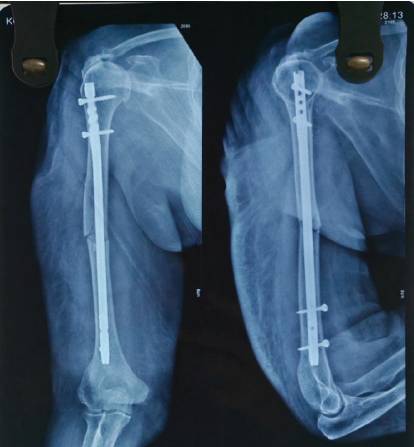

Reduction was confirmed fluoroscopically. Soft-tissue dissection was kept to the minimum required. The wound was thoroughly irrigated, hemostasis achieved, and the rotator cuff repaired carefully. The deltoid interval was closed, and sterile dressings were applied. Post-operative X-ray showed stable fixation (Fig. 4).

Figure 4: Immediate Post-operative X-ray showing nail in situ.

The patient was supported in a sling, and from the 1st post-operative day, she began elbow, wrist, and hand exercises. Passive shoulder mobilization was initiated on day 2. Regular dressing was done. Staples were removed on POD-14. Patient’s range of motion (ROM) improved progressively and attained nearly full ROM by 6th week postoperatively, and X-ray showed good bony union (Fig. 5).

Figure 5: One month old post-operative X-ray showing good bone union.